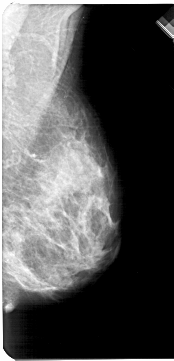

A_1213_1.LEFT_CC

LEFT_CC LINES 5176 PIXELS_PER_LINE 2671 BITS_PER_PIXEL 12 RESOLUTION 43.5 OVERLAY